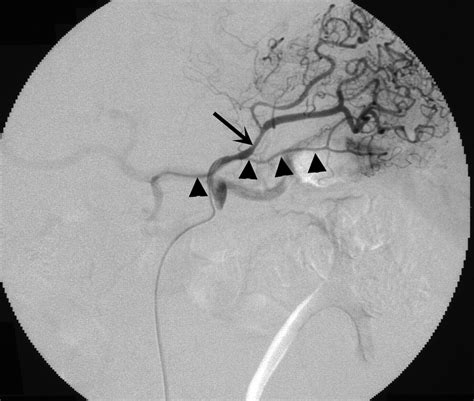

Imaging techniques play a vital role in evaluating the health and patency of the Left Gastric Artery. Computed Tomography (CT) scans with contrast enhancement are the gold standard for visualizing the vessel’s diameter and identifying any aneurysms or atherosclerotic changes. In cases of acute hemorrhage, angiography allows for both the diagnosis and immediate therapeutic intervention via transcatheter arterial embolization.

Physicians must maintain a high index of suspicion for vascular involvement in patients presenting with hematemesis or melena. Early identification of the vessel status through diagnostic imaging can guide the treatment team toward the most effective management strategy, whether it be endoscopic clipping, surgical ligation, or endovascular embolization.